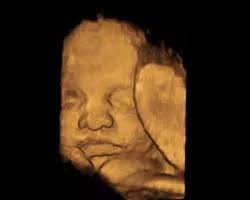

Com 34 semanas de gravidez a tão esperada hora de ter o seu bebê no colo finalmente está se aproximando. Su bebé está actuando como un niño. Mantiene los ojos abiertos cuando está despierto y los cierra cuando duerme.

Mas o melhor mesmo é ficar lá dentro por umas boas semanas até pelo menos 39 semanas e de preferência até o momento em que quiser nascer. Os pulmões e o sistema nervoso do bebê. Aprende todo lo relacionado con el desarrollo de tu bebé y los cambios en tu cuerpo a las 34 semanas de embarazo. Si el escroto de tu bebé parece muy grande al nacer no te preocupes. Síntomas frecuentes en la semana 34 de embarazo. Mide unos 437 cm de largo en promedio y pesa unos 2080 gramos en promedio. En la semana 34 de embarazo notas que tu cuerpo tiene que adaptarse a los cambios que ocasiona el embarazo. La hinchazón se debe al líquido adicional y disminuirá luego de. Mide 45 cm como el ancho de un microondas y pesa 2150 g como un pack de 6 latas de refresco.

Sus pulmones ya pueden funcionar en el exterior. Escrito por Jade Magdaleno matrona. O seu bebê está com cerca de 40cm e 2kg o desenvolvimento está quase completo. Hola chicas espero esten super bien. Aprende todo lo relacionado con el desarrollo de tu bebé y los cambios en tu cuerpo a las 34 semanas de embarazo. El cuerpo se está preparando para el parto. 232 a 238 dias de gestação Na 34ª semana de gestação os pulmões do bebê já estão completamente formados mas ainda estão na fase de amadurecimento produzindo o surfactante pulmonar que é uma substância importante para facilitar a troca dos gases.